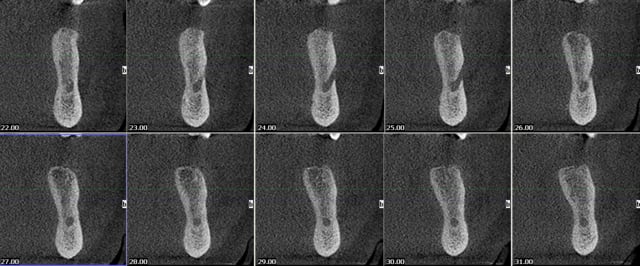

vite fait quelques copies d'écran de la Gendex CB 500 acquise il y a un an (avec le capteur de 1 ere génération)

Les modèles vendus actuellement ont un capteur optimisé pour les panos

pour les secteurs molaires